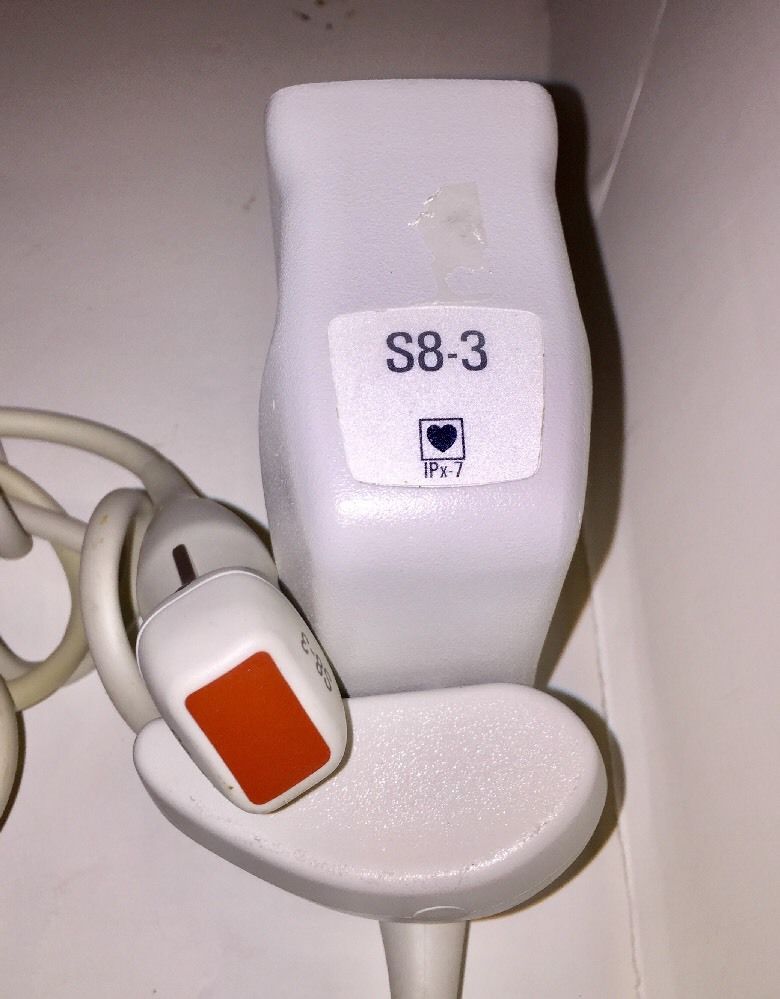

Philips S8-3 Ultrasound Transducer Probe

Sale price$ 14,387.70